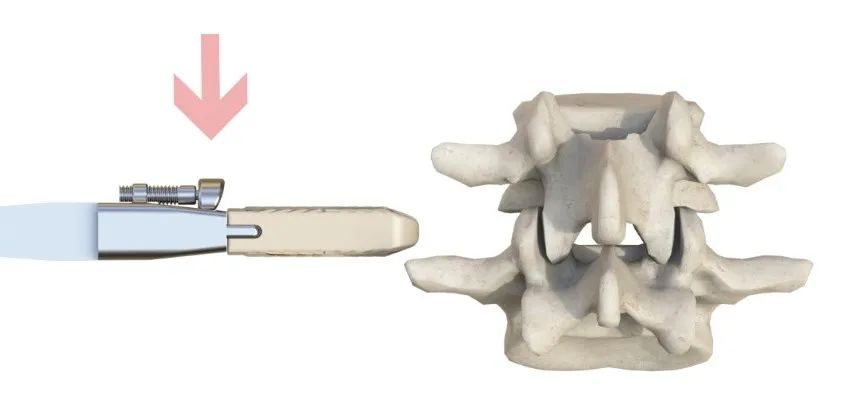

預(yù)彎的固定夾設(shè)計,交叉式自導(dǎo)向打入

安全簡單的操作方式

限深可調(diào),融合器植入位置更精準

固定夾敲入即鎖緊,操作更簡單

降低對椎體邊緣骨贅處理要求,縮短手術(shù)時間